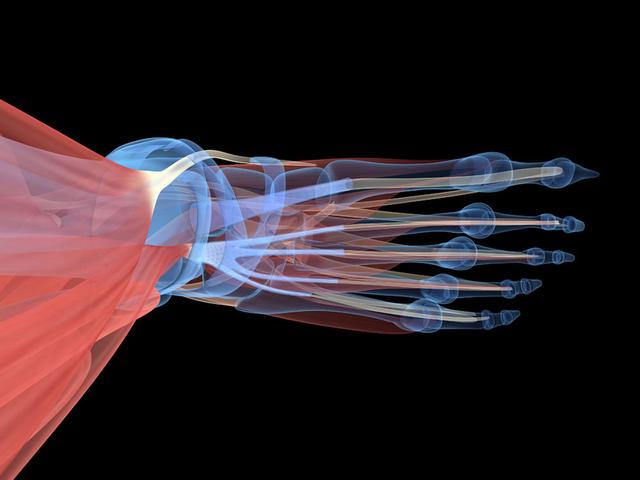

从一方面来说,人类是弱小的,容易生病,容易受伤,但从另一方面来说,人类也是强大的...